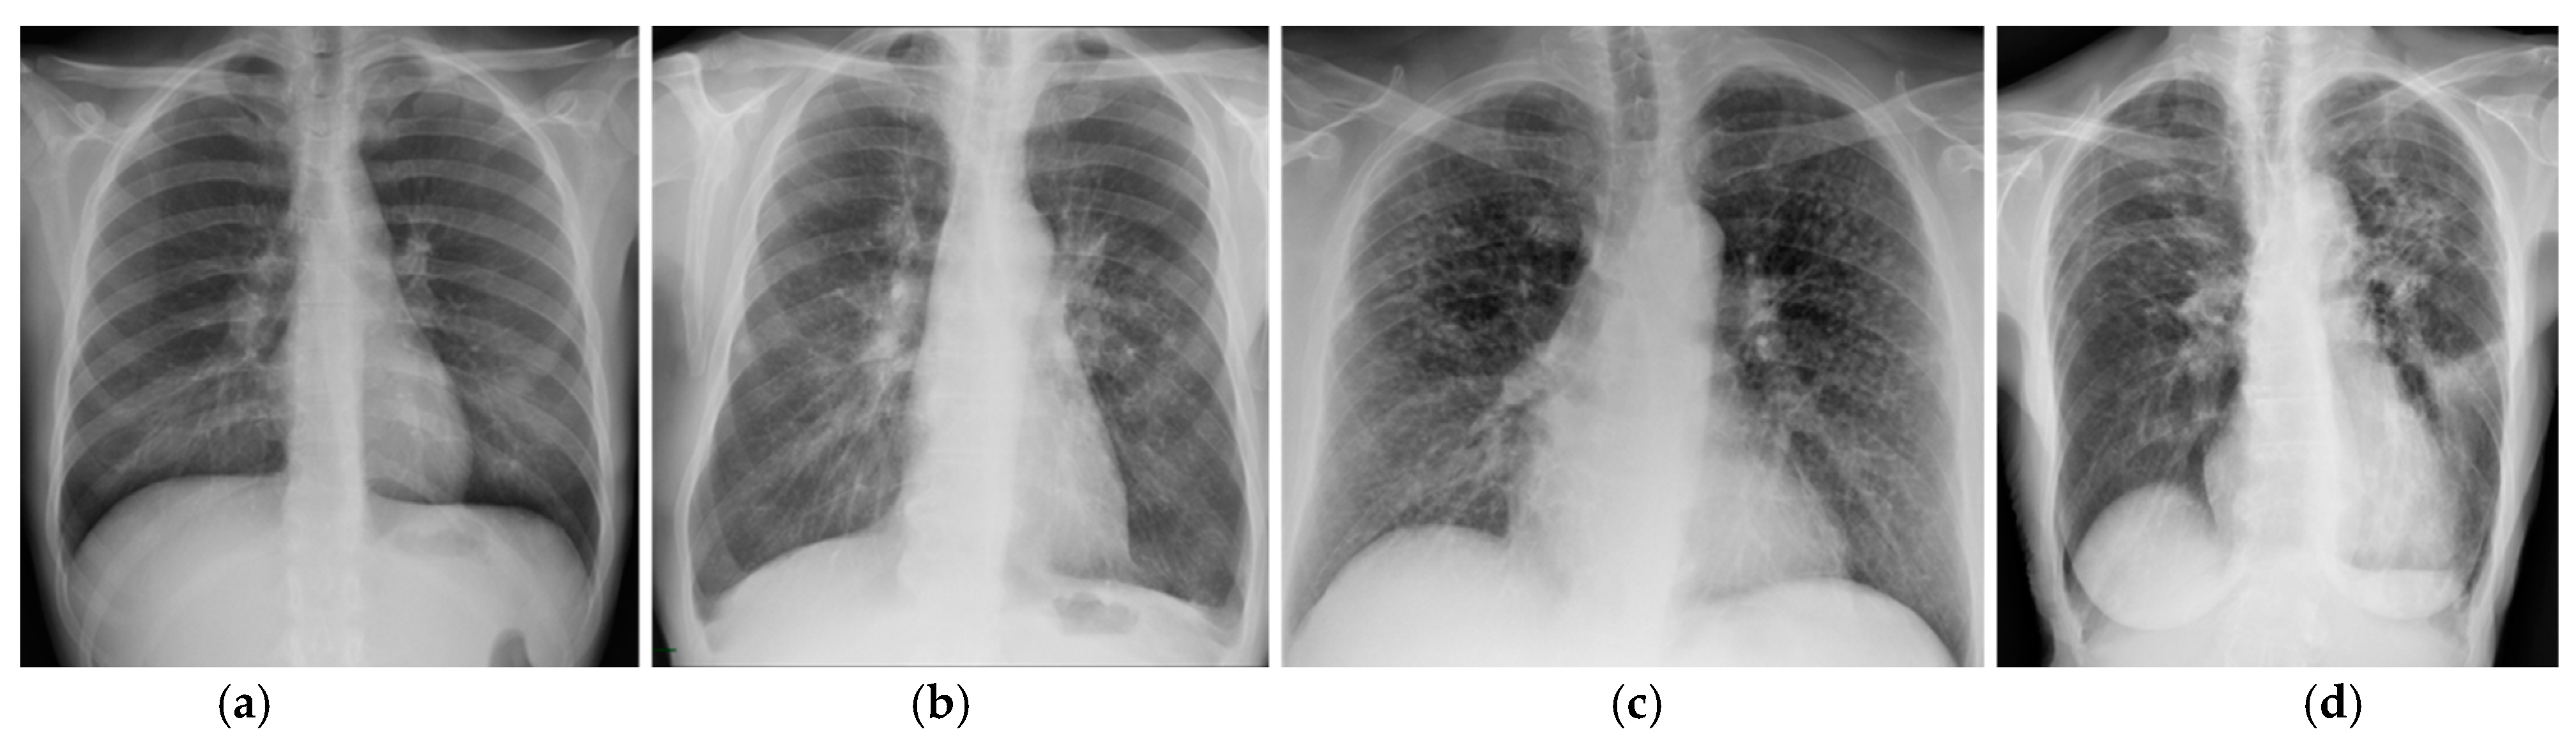

Prognostic assessment in sarcoidosis still relies on the Scadding staging system based on CXR findings (Table 2) [4]. As showed in Table 2, this system is related to the likely disease course, with percentage of resolution in untreated patients decreasing as Scadding stage increases. Spontaneous resolution happens in 50–90% of patients with only lymph node enlargement (stage I disease). Gradual reduction in lymph node size usually occurs in the first 3 to 6 months and complete resolution may happen within 2 years. In the remaining cases, parenchymal opacities can emerge as lymph nodes decrease in size. Percentage of resolution in untreated patients decreases by nearly 20% from Scadding stage I to stage II—lymph node enlargement with parenchymal changes—and stage III—only parenchymal abnormalities. Fibrotic changes represent the end-stage of this disease (stage IV) and do not resolve [3,4] (Figure 3).

Figure 3.

CXR of patients with thoracic sarcoidosis. (a) Scadding stage I showing bilateral hilar enlargement. (b) Scadding stage II showing bilateral hilar enlargement and parenchymal reticulation and micronodules. (c) Scadding stage III showing bilateral micronodules without significant hilar enlargement. (d) Scadding stage IV showing upward retraction of hila with bronchial distortion and reticular opacities.

Current guidelines in management of sarcoidosis recommend serial chest radiography—evaluating possible shifts in the Scadding staging—and PFTs (pulmonary function tests) in order to detect changes in disease severity [2,4]. Nevertheless, several limitations come with this four-level staging system based on radiographic appearance, despite its wide application in the past nearly sixty years. Firstly, thoracic abnormalities may not necessarily follow the Scadding staging order [31]. Secondly, changes in the staging do not take into consideration changes in radiographic disease extent [3]. Lastly, the main limitation of the Scadding staging system is subjectivity: some features on chest radiography have variable appearance, including lung fibrosis that may range from subtle radiographic signs to end-stage diffuse fibrosis, leading to poor inter-observer agreement [3,33]. Yet, proper identification of fibrotic abnormalities is essential for an adequate management of sarcoid patients [4]. The limits of the Scadding system represent the basis for implementing new techniques and exploring new approaches to improve the prognostic evaluation of sarcoid patients just like it is happening in other ILD [34].